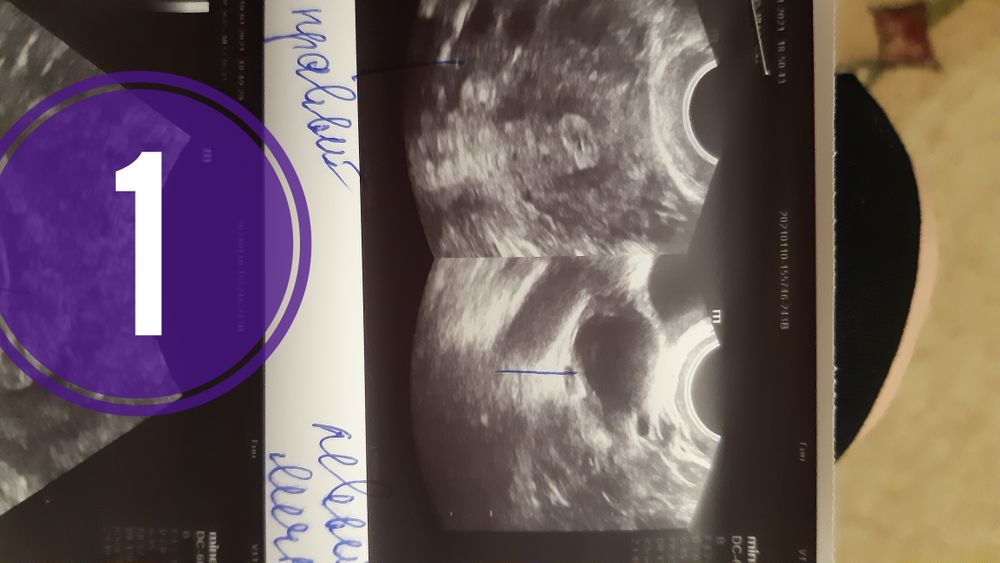

Фолликулометрия. Два разных узи.

6янв (11дц) узи -доминантный ф.15,5 в левом яичнике.

Под цифрой 1 узи 9янв вечером, где пишут-желтое тело 20мм. Тесты при этом только начанают ярчать, но пика еще не было. Потом в 20.30 тест //

Под цифрой 2 узи в другом месте сегодня с утра 10 янв. Описание-доминантный фолликул 24на20мм. Тест с утра также //. Врач сказала, жди О сегодня-завтра.

На первом фото очень уж похоже все таки на ЖТ, а вот второе больше на ДФ, а сегодня врач смотрел кровоток?

Фото мелкие, надо поближе. Но с такими фото вообще похоже на персистирующий фолликул